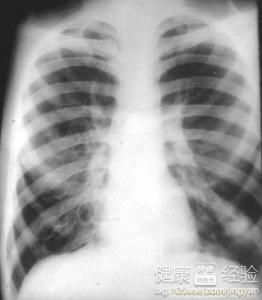

支氣管炎是一種常見的呼吸系統(tǒng)疾病,其癥狀包括咳嗽、咳痰、呼吸急促等,許多患者關(guān)心的問題是:支氣管炎能自愈嗎?本文將詳細(xì)解析支氣管炎的類型、癥狀、治療方法以及能否自愈的問題,幫助患者更好地了解并應(yīng)對這一疾病。

支氣管炎是指氣管、支氣管黏膜及其周圍組織的炎癥,根據(jù)其發(fā)病的急緩,可分為急性支氣管炎和慢性支氣管炎,急性支氣管炎通常由于病毒、細(xì)菌等感染引起,癥狀明顯且病程較短;而慢性支氣管炎則由于長期吸煙、空氣污染等因素導(dǎo)致,癥狀持續(xù)較長時間,易反復(fù)發(fā)作。

支氣管炎的癥狀

支氣管炎的典型癥狀包括咳嗽、咳痰、呼吸急促等,部分患者可能伴有發(fā)熱、胸悶等癥狀,咳嗽通常為首發(fā)癥狀,隨著病情的發(fā)展,逐漸出現(xiàn)咳痰,痰量可能因病情嚴(yán)重程度而異,在嚴(yán)重的情況下,患者可能出現(xiàn)呼吸困難、喘息等癥狀。